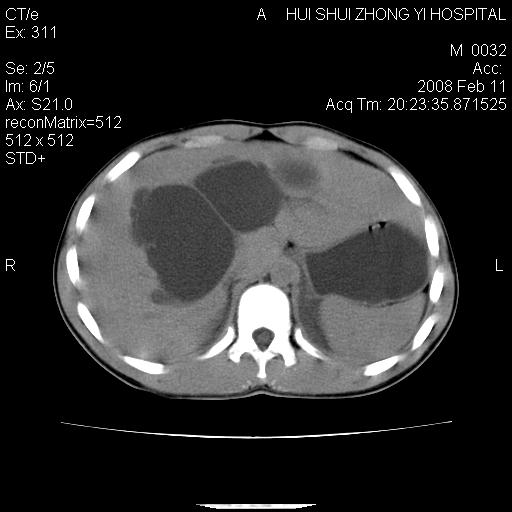

8年前曾在贵洲省人民医院b超诊断为肝内胆管结石。现腹痛剧烈,现发烧、头痛、恶心呕吐县医院b超示胆囊肿大大小159*46mm,囊内见6*5mm强回声光团,胆各总管内径56mm。提示:胆囊结石、急性胆囊炎、胆总管重度扩张。

胆囊结石.急性胆囊炎.重度胆管扩张.右侧胸腔少量积液,建议ct增强

考虑先天性胆管囊肿;胆囊增大并结石。右侧胸腔少量积液,建议ct增强。

caroli囊肿并囊内结石。胆囊增大并胆结石。典型!

先天性胆管囊肿,胆囊结石、胆囊增大,右侧少量胸腔积液。